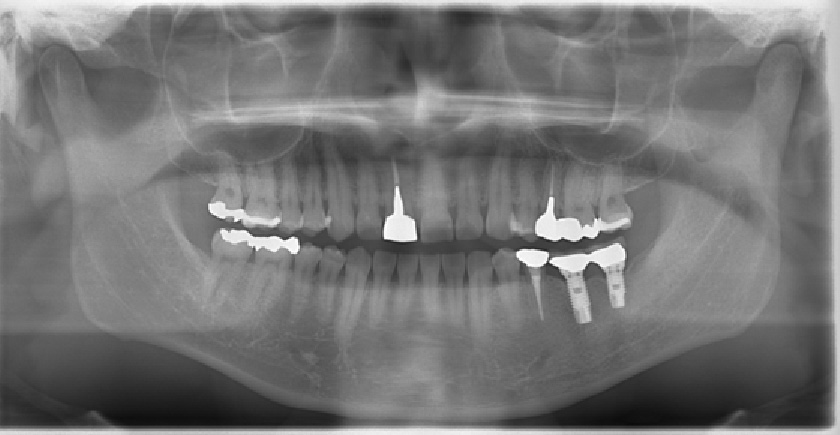

• 術前術後のレントゲン写真

写真向かって、右下の奥歯が割れてしまっているので、抜歯し、そこに人工歯根として、インプラントを埋め込んだレントゲン写真です。

• 術後

術後